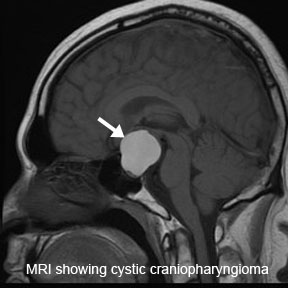

颅咽管瘤 是起源于神经上皮的肿瘤,由鳞状细胞沿原颅咽管道长出。它们的发病率在每10万人年0.5至2.5之间,不因性别或种族而有所不同。颅咽管瘤占全部颅内肿瘤的1.2%至4.6%。它们呈...

颅咽管瘤 是一种少见的中枢神经系统(CNS)良性肿瘤,被认为是由脑垂体附近的Rathkes囊残余形成。它们占全部原发性中枢神经系统肿瘤的不到1%,但却是儿童较常见的颅内非神经胶质肿瘤...